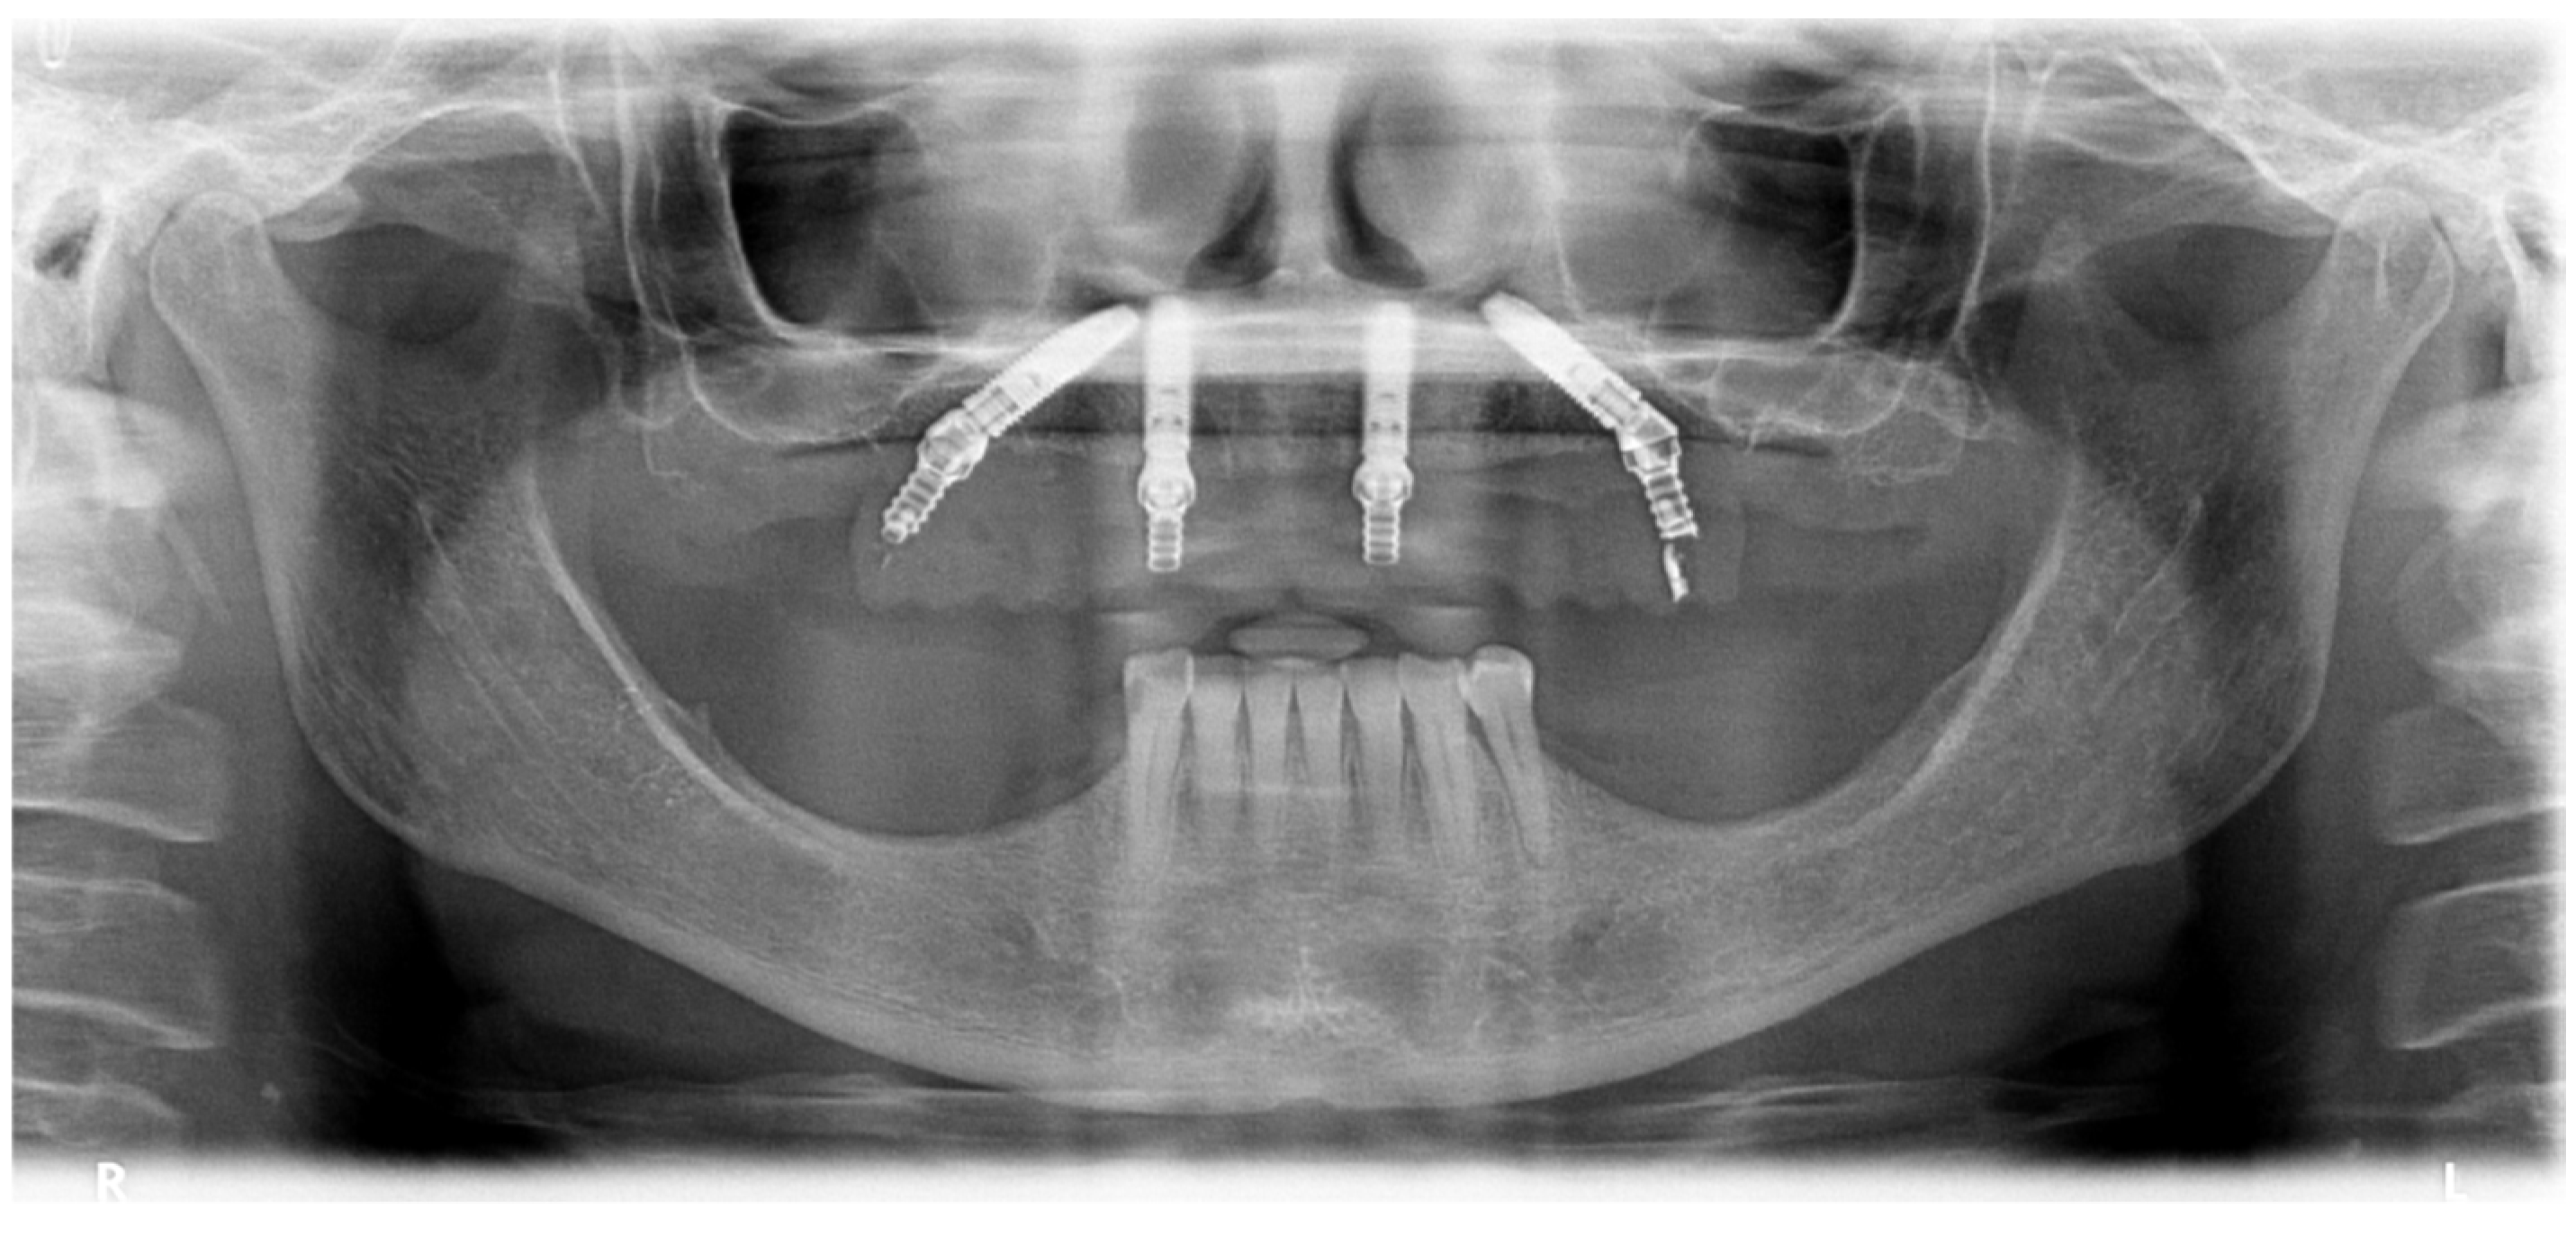

2.1. Patient 1